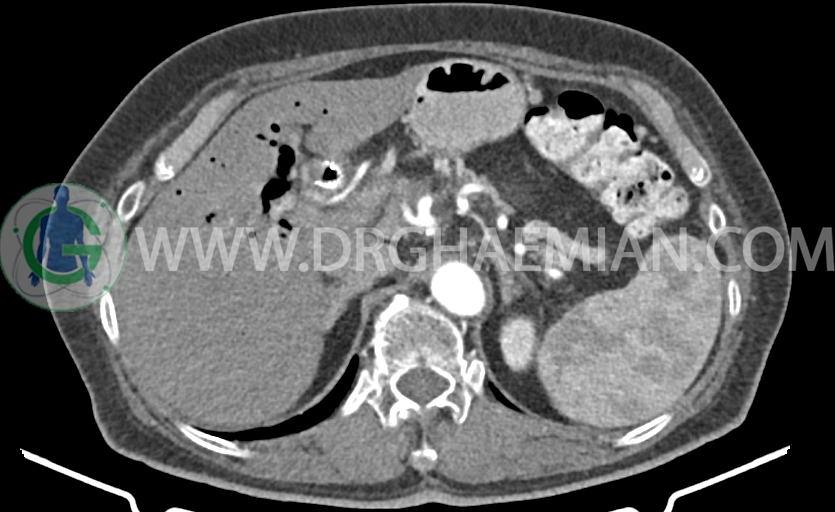

سی تی اسکن شکم و لگن از تشعشعات برای ایجاد تصاویر عرضی مقطعی از شکم و نایحه بین استخوان های لگن استفاده میکند. در این کیس سرطان پانکراس، اتروفی پانکراس، آسیت در ناحیه لگن و کلسیفیکاسیون شریان آئورت و ایلیاک دیده می شود.

در سی تی اسکن اسپیرال شکم و لگن با و بدون کنتراست خوراکی و وریدی- پروتکل پانکراس (مولتی دیدکتور 16 با مقاطع ظریف و بازسازی های ساژیتال و کرونال) :

– Stent در CBD

–دانسیته هوا در CBD و مجاری صفراوی داخل و خارج کبدی و کیسه صفرا (ثانویه به دستکاری)

–مجاری صفراوی داخل کبدی مختصر دیلاته است.

-CHD دیلاته (20mm)

– توده هیپودنس ill – defined با حداکثر دیامتر تقریبی 50mm در ناحیه گردن و پروگزیمال body پانکراس( بدون تغییر قابل توجه در سایز نسبت به سی تی اسکن 1401/9/17 )

همراه با encasement در SMA ،SMV، شریان اسپلنیک، شریان هپاتیک و پروگزیمال ورید پورت (بدون تغییر نسبت به سی تی اسکن 1401/9/17)

– اتروفی دیستال پانکراس (بدون تغییر نسبت به سی تی اسکن 1401/9/17)

– شواهد فوق مطرح کننده ضایعات malignant پانکراس ( آدنوکارسینوم ) می باشد که بر اساس معیار های

NCCN ،localy advanced و unresectable می باشد.

– لنف نودهای متعدد با حداکثر SAD=6mm در اطراف توده فوق الذکر، پانکراس و مزانتر (بدون تغییر قابل توجه نسبت به سی تی اسکن 1401/9/17)

-Fat stranding در اطراف پانکراس و فضاهای مزانتر در Mid line و Mid abdomen

– Fullness در سیستم پیلوکالیسیل کلیه ها (بیشتر سمت چپ) احتمالاً فاقد اهمیت بالینی است و نسبت به سی تی اسکن قبلی بهبود نشان می دهد.

–پرومیننسی عروق لگنی، بدون تغییر نسبت به سی تی اسکن قبلی) (?Pelvic congestion syndrome )

-مایع آسیت اندک در حفره لگن (کاهش نسبت به سی تی اسکن قبلی)

-کلسیفیکاسیون جدار آئورت و ایلیاک

–نمای شبیه به افزایش ضخامت جداری Circumferential در ناحیه آنتروپیلور معده با نمای غیراختصاصی دیده شد.